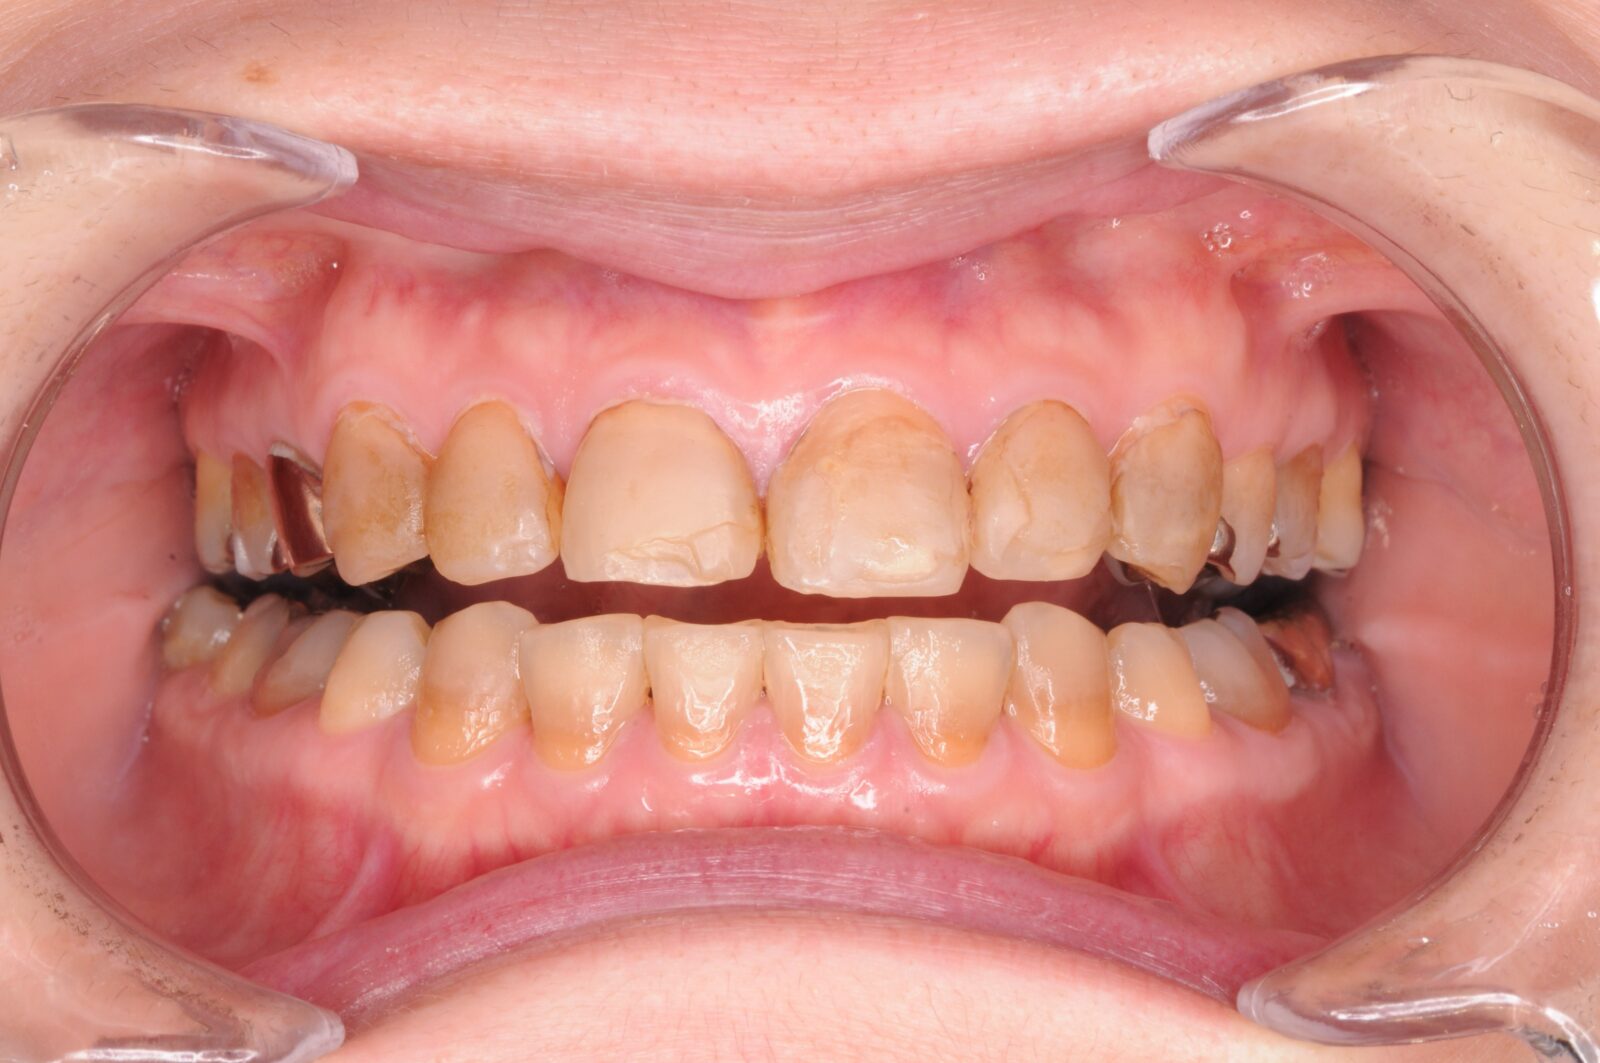

治療前 治療後

全顎的治療(インプラント+矯正)

臼歯部の根尖病巣と咬合状態の不整があり、全体的な治療を希望。   歯根破折や以前の根管治療時の穿孔などにより、保存不可能な臼歯部を抜歯。   事前にシミュレーションしておいた矯正治療後の歯の並びをもとに、適切な位置にインプラント埋入。   …